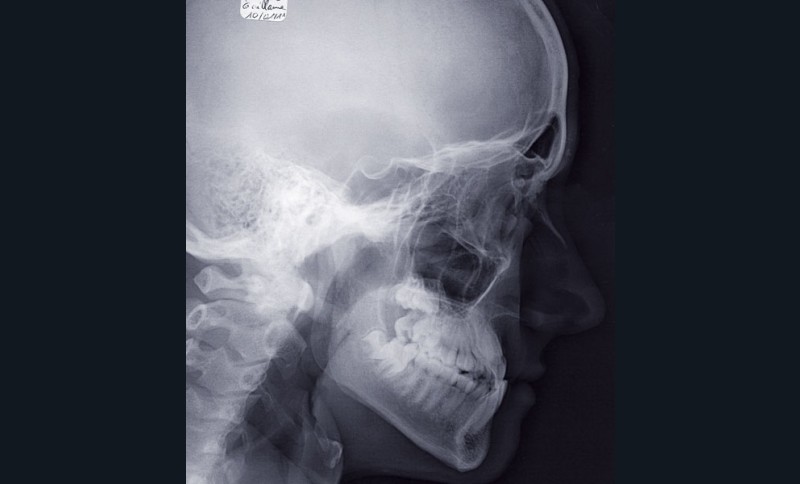

Les valeurs céphalométriques sont :

FMA : 19° ;

IMPA : 86° ;

SNA : 79° ;

SNB : 82° ;

ANB : -3° ;

Ao-Bo : -10,5 mm ;

I/F : 115° ;

I/i : 139° ;

Pl.Occ/Francfort : 7°

Total Chin : 12,5 mm ;

Upper Lip : 15,5 mm ;

Angle Z : 85°

HFP : 50 mm ;

HFA : 58.5 mm.